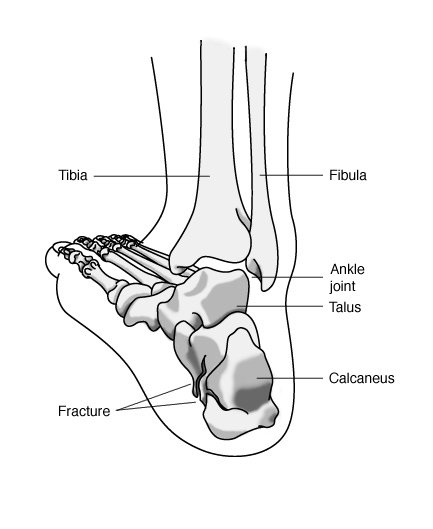

Heel Fractures

It’s not easy to break your heel bone (calcaneus). Because it takes a lot of force, such as that sustained in a motor vehicle accident or a fall from a height, you may also incur other injuries as well, particularly to the back.